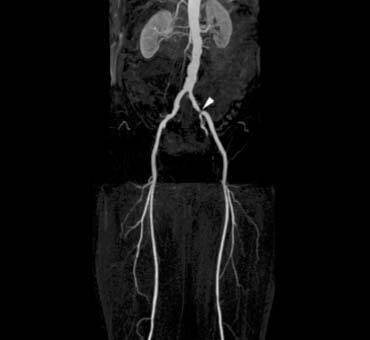

CT angiografie

Een CT Angiografie is een CT-scan van de bloedvaten. Een CT-scan is een onderzoek dat met behulp van röntgenstralen opnamen maakt van het lichaam.

Omdat dit middel de röntgenstralen tegenhoudt worden de bloedvaten op de CT-scan zichtbaarder gemaakt. De beelden die gemaakt worden geven gedetailleerdere informatie over de bloedvaten. Zo kunnen bijvoorbeeld vernauwingen, verstoppingen en verwijdingen (aneurysma’s) worden opgespoord.